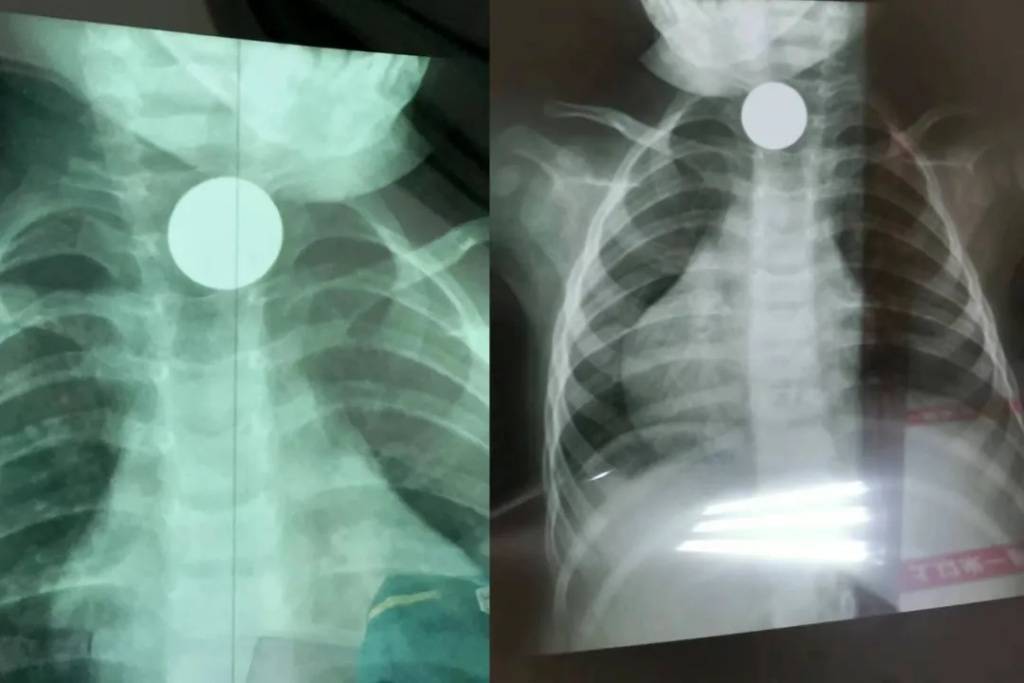

小青发现女儿最近像被戳破的气球,脸蛋上的婴儿肥以肉眼可见的速度消失。才六岁的孩子,原本肉嘟嘟的手腕突然能摸到清晰的骨头,饭桌上扒拉两口就放下筷子,夜里还总捂着肚子哼哼。起初她以为是夏天天热没胃口,直到某天给孩子洗澡时,摸到女儿后背硌手的脊椎骨,才吓得连夜抱起孩子往医院冲。拍片室里的警报声像针一样扎进耳朵。"摘项链!"医生头也不抬地递过铅衣,小青的手僵在半空——女儿从出生起就没戴过任何饰品。夫妻俩把孩子扒拉得像翻口袋,连头发丝都检查了三遍,仪器却还是固执地"滴滴"作响。换了台机器结果依旧,医生皱眉推进孩子:"先拍再说。"片子洗出来时,所有人倒抽冷气:孩子胸腔里赫然嵌着块指甲盖大的磁铁,在X光下泛着冷光,位置正好在脖颈下方,活像戴了条隐形的金属项链。手术台上,医生用内窥镜夹出磁铁时还在念叨:"再晚来几天,这东西就能穿透肠壁。"小青这才想起,上周整理储藏室时翻出的磁力片玩具,少了最中间那块星星形状的。她总以为孩子大了不会乱吃东西,却忘了六岁正是把"探索世界"理解为"放进嘴里尝尝"的年纪。病房里,看着女儿打着点滴熟睡的脸,她把家里所有小物件全塞进了带锁收纳箱,连冰箱贴都用胶带固定在高处。这事过后,小区妈妈群炸开了锅。有人说自家孩子吞过纽扣电池,有人晒出孩子误吞钢珠后的X光片。医生的话在家长圈里疯传:"5岁以下孩子的食道比吸管还细,一块磁铁就能要了命。"现在小青去朋友家做客,第一件事就是扫视茶几——花生、硬币、胸针,这些在大人眼里的小玩意,在孩子手中都可能变成凶器。那天从医院回家,她在玄关贴了张纸条:"进门前先检查口袋,别把小零件带回家。"毕竟孩子的好奇心不会停,但家长的警惕性,一秒都不能松懈。